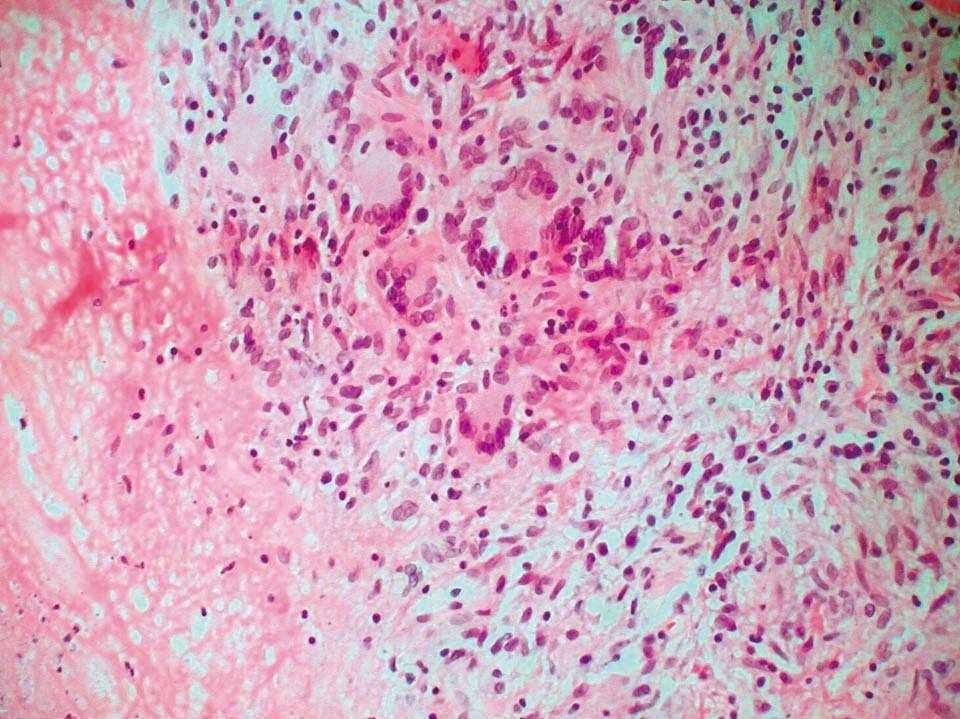

En la tabla 2 se exponen los datos referentes a las pruebas diagnósticas (estudio histopatológico, microbiológico, analítico, Mantoux y hallazgos radiológicos), tratamiento pautado y respuesta terapéutica. Se realizó estudio microbiológico de material purulento en los 6 casos y estudio histopatológico en la mitad. En todos los cultivos de material purulento (6) y de muestra de biopsia (3) se observó crecimiento en medio de Löwenstein-Jensen de colonias de Mycobacterium tuberculosis. Sin embargo, no se detectaron BAAR con la tinción de Auramina en 5 de los 6 casos de material purulento ni con la tinción de Ziehl-Neelsen en dos de las tres muestras de biopsia. El estudio histopatológico (3) mostró granulomas compuestos de células epitelioides, células gigantes de tipo Langhans rodeadas por linfocitos, en dos casos granulomas caseificantes (fig. 2) y no caseificantes en el otro. Entre los estudios de laboratorio, incluidos hemograma, bioquímica completa y análisis de orina, sólo destacaban en algún paciente datos propios de sus enfermedades o hábitos tóxicos previos. En dos la velocidad de sedimentación globular (VSG) fue alta.

Figura 2. Paciente número 5. Granulomas epitelioides con necrosis central (hematoxilina-eosina ×150).